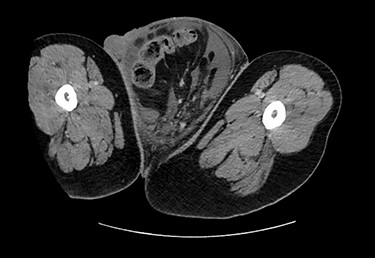

Testicular ultrasound revealed a large left inguinal hernia with a fluid-filled hernia sac surrounding one or more segments of the intestine within the scrotum, measuring >15 cm. The left testis could not be identified. The right testis appeared normal on imaging but was displaced superiorly and medially by the large left scrotal hernia sac. The right testis demonstrated color Doppler signals and arterial Doppler waveform. Computed tomography (CT) revealed a large left inguinal hernia sac with bowel, fluid and Left ureter within it associated with left-sided hydronephrosis and severe cortical thickening. Figures 2 and 3 demonstrate pertinent CT images.

CT (axial view) demonstrating large left inguinal hernia sac containing bowel, fluid and left ureter.